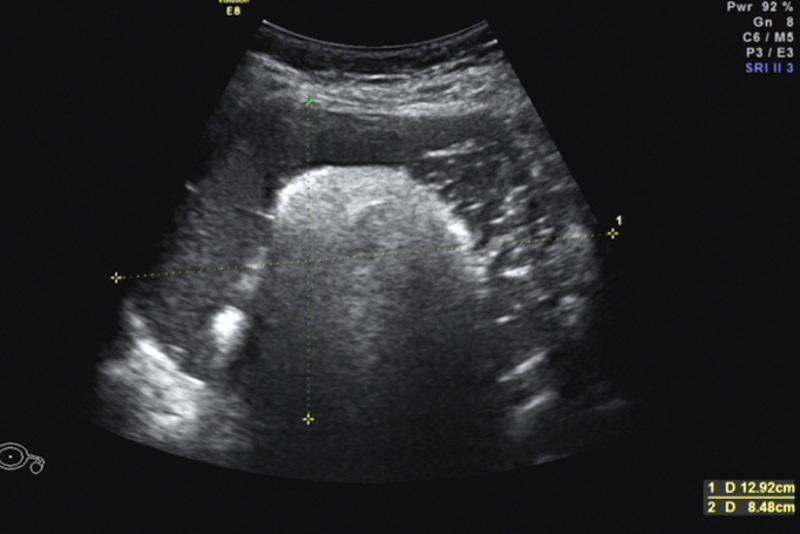

今年1月,石女士驚喜地發(fā)現(xiàn)自己懷孕了,然而在之后的孕檢過程中,檢查發(fā)現(xiàn)右附件區(qū)有一大小125mm×115mm×79mm囊性占位,混合回聲,考慮右側(cè)卵巢成熟畸胎瘤。由于囊腫巨大,內(nèi)部回聲雜亂,隨著孕期的增加,囊腫有可能發(fā)生扭轉(zhuǎn),導(dǎo)致破裂引起急性腹痛威脅母嬰安全。同時,巨大的腹腔占位可能影響子宮增大,限制胎兒的生長……

因患者腫塊巨大,孕期手術(shù)風(fēng)險高,醫(yī)院立即組織了婦科、產(chǎn)科、放射科、超聲醫(yī)學(xué)科、麻醉科、藥學(xué)部等開展了MDT會診?;颊吣倚哉嘉恢杏写笮〖s7cm的實性占位,手術(shù)需要考慮盡量減少手術(shù)后腹腔黏連,同時需要將占位完整切除,盡量減少對腹腔和子宮的干擾,才能最大程度保證孕期平穩(wěn)和母嬰安全,經(jīng)過全面考慮和深入討論,專家團(tuán)隊為患者制定了詳細(xì)的治療方案,決定行經(jīng)臍單孔腹腔鏡下行卵巢囊腫剔除手術(shù)。